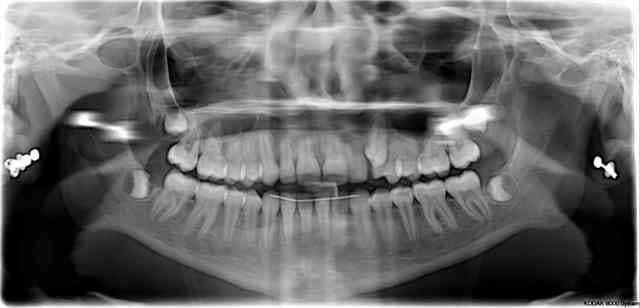

Et là, peut on parler de rhisalyse? Patient avec une superbe occlusion, afmp trés petits et éhgaux et je pense que ca le sauve pour l'instant

T'es sûr que c'est la Rx "après traitement" ?????

Scandaleux.

---> je crois qu'un peu plus de modération conviendrai car à part un pb sur 12 et 11 avec poche paro, le reste me semble normal. Une rhizalyse ne constitue pas un atermoiement tel qu'on peut le lire sur le forum.

et l'alignement de la 23 ? ( sans parler des axes 24-25 )........